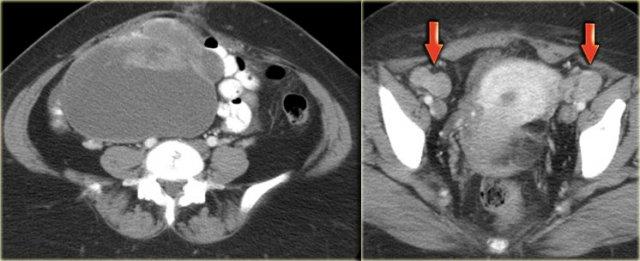

Siêu âm cho thấy một khối đặc-nang phức tạp ở buồng trứng trái, và một khối đặc-nang phức tạp khác có kích thước rất lớn ở nửa chậu hông phải.

CT của cùng bệnh nhân cho thấy một khối đặc-nang phức tạp với các vách dày có ngấm thuốc ở buồng trứng phải.

Các đặc điểm này rất nghi ngờ cho một u nang buồng trứng ác tính.

Ngoài ra còn có hạch bạch huyết to hai bên (mũi tên).

Kết quả giải phẫu bệnh cho thấy đây là ung thư biểu mô tuyến nang thanh dịch buồng trứng.

Đây là loại ung thư buồng trứng thường gặp nhất.

Trên siêu âm, cả hai buồng trứng đều to rõ rệt và chứa các thành phần nang với các thành phần đặc trong lòng nang (mũi tên).

Các tổn thương đặc-nang phức tạp, kết hợp với tính chất hai bên, rất nghi ngờ cho u nang buồng trứng thực sự và cần được đánh giá thêm.

Một lần nữa, vai trò của chẩn đoán hình ảnh là xác nhận sự hiện diện của tổn thương và kết luận rằng đây không phải là tổn thương có thể được phân loại chắc chắn là lành tính, cũng không phải là tổn thương có thể theo dõi an toàn: cần phải có hành động can thiệp.

CT của cùng bệnh nhân xác nhận các tổn thương đặc-nang phức tạp hai bên kích thước lớn, phồng vào ổ bụng.

Mục đích của CT không phải là xác nhận những gì đã biết từ siêu âm, mà là để phân giai đoạn bệnh.